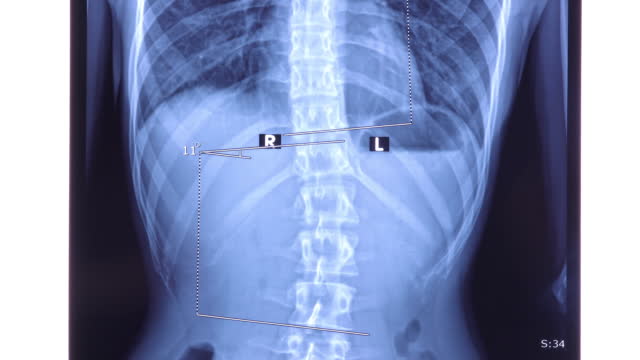

척추측만증은 허리가 옆으로 휘어진 상태를 나타내는 질환으로, 특히 청소년기에 많이 발생하는 허리의 변형이며 척추의 측만(옆으로) 휘어짐을 특징으로 합니다. 이 질환은 주로 10도 이상의 각도로 허리가 휘어질 때 측만증으로 분류됩니다.

척추측만증은 초기에는 치료가 뚜렷하게 정해져 있지 않으며, 조기 발견과 조기 치료가 중요합니다. 20도 미만의 각도로 허리가 휘어진 경우에는 운동, 체조, 바른 자세 유지, 근육 강화 운동 등으로 관리할 수 있습니다. 그러나 20도 이상이 되면 더 진행될 가능성이 높으므로 보조기를 사용하거나 각도가 50도 이상일 때 허리를 교정하는 수술을 고려해야 합니다.